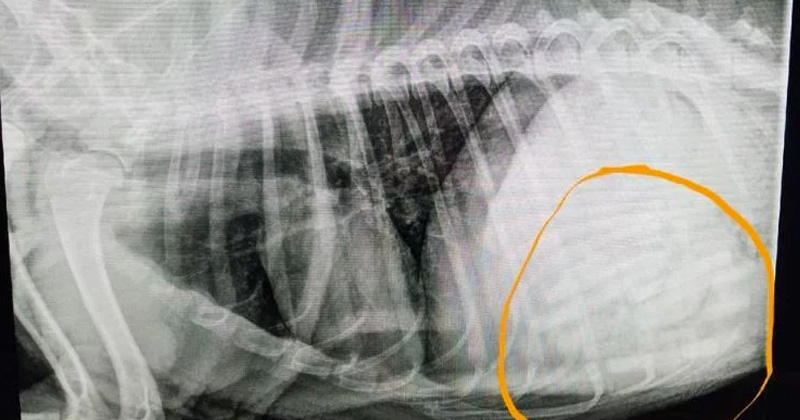

Extraen 21 chupones del estómago de un perro

La amada mascota devoraba a escondidas de sus dueños los chupones del bebé de la familia